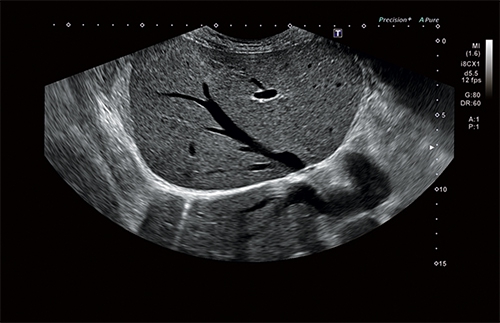

Ультразвуковая система Aplio i700 обеспечивает лучшее качество диагностики за максимально короткое время. Сочетая превосходное качество изображений с исключительной простотой использования и большим выбором программных и аппаратных опций, модель i-серии Aplio 700 является универсальным ультразвуковым прибором.

Универсальная УЗИ система «Кэнон Тошиба Аплио i700» премиального класса может похвастаться новейшими технологическими решениями, множеством современных режимов и программным обеспечением высшего порядка. Все это позволяет достичь поистине невероятного качества сканирования, визуализации и детализации. Этот многофункциональный сканер нового поколения создан для решения самых сложных задач в обширном спектре направлений медицинской деятельности.

• Режим Luminance для получения качественного изображения плода в первом триместре с помощью трехмерной реконструкции

4D

Объемное сканирование в реальном времени больше не фантастика, а впечатляющее достижение современных технологий. С помощью сканирования этого типа вы сможете рассмотреть даже самые мелкие детали изображения под любым требуемым для проведения исследования углом.